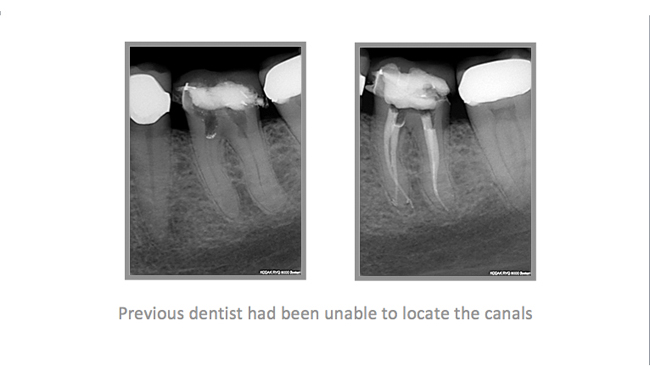

• A few Teeth Treated by Dr. Katsarsky

• A few Cases Treated by Dr. Katsarsky